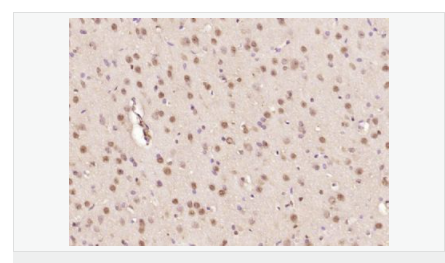

| 產(chǎn)品應(yīng)用 | ELISA=1:5000-10000 IHC-P=1:100-500 IHC-F=1:100-500 ICC=1:100-500 IF=1:100-500 (石蠟切片需做抗原修復(fù)) not yet tested in other applications. optimal dilutions/concentrations should be determined by the end user. |

| 細胞定位 | 細胞核 細胞漿 |

| 產(chǎn)品介紹 | The human ataxin-7 gene, also known as spinocerebellar ataxia 7 or SCA7, maps to chromosome 3p13-p12, has a 2,727-bp open reading frame, and encodes a 892 amino acid protein containing a nuclear localization signal and a polyglutamine tract (1,2). SCA7 is an autosomal dominant neurodegenerative disorder characterized by ataxia and selective neuronal cell loss caused by the expansion of a translated CAG repeat encoding a polyglutamine tract in ataxin-7, which is the SCA7 gene product (3,4). Ataxin-7 is expressed within neurons both affected and unaffected in SCA7 pathology with subcellular localization being variable depending upon the neuronal subtype (5). Polyglutamine expanded in ataxin-7 may carry out its pathogenic effects in the nucleus by altering the matrix-associated nuclear structure and/or by disrupting nucleolar function (6). Function: Ataxin 7 is a protein of unknown function. It may be the human orthologue of the yeast SAGA SGF73 subunit and a subunit of the human TFTC-like transcriptional complexes. Spinocerebellar ataxia 7 (one of a group of hereditary neurodegenrative diseases) is caused by an expanded trinucleotide repeat in the gene encoding ataxin 7. Ataxin 7 is typically located in the cytoplasm and on the nuclear membrane of normal brain neurons. In cells where there is a mutation of the SCA7 gene, ataxin 7 accumulates in intranuclear inclusions and can result in cell death. Subunit: Component of the STAGA transcription coactivator-HAT complex, at least composed of SUPT3H, GCN5L2, TAF5L, TAF6L, SUPT7L, TADA3L, TAD1L, TAF10, TAF12, TRRAP, TAF9 and ATXN7. The STAGA core complex is associated with a subcomplex required for histone deubiquitination composed of ATXN7L3, ENY2 and USP22. Interacts with SORBS1, PSMC1 and CRX. Interacts with TRRAP, GCN5L2 and TAF10. Interacts with alpha tubulin. Subcellular Location: Cytoplasmic (isoform b) and Nuclear (isoform a) Tissue Specificity: Isoform a and isoform b are expressed in CNS, but isoform a is expressed predominantly in the peripherical tissues. Isoform b is also highly expressed in the frontal lobe, skeletal muscle and spinal cord and is expressed at a lower level in the lung, lymphoblast and intestine. Post-translational modifications: Proteolytically cleaved. The cleavage may be involved in SCA7 degeneration: the isoform fragments may exert distinct toxic influences that could contribute to selective neurodegeneration. Sumoylation decreases the aggregation propensity and cellular toxicity of forms with an expanded poly-Gln region but has no effect on subcellular location or interaction with components of the STAGA complex. DISEASE: Defects in ATXN7 are the cause of spinocerebellar ataxia type 7 (SCA7) [MIM:164500]; also known as olivopontocerebellar atrophy III (OPCA III or OPCA3) or olivopontocerebellar atrophy with retinal degeneration. Spinocerebellar ataxia is a clinically and genetically heterogeneous group of cerebellar disorders. Patients show progressive incoordination of gait and often poor coordination of hands, speech and eye movements, due to degeneration of the cerebellum with variable involvement of the brainstem and spinal cord. SCA7 belongs to the autosomal dominant cerebellar ataxias type II (ADCA II) which are characterized by cerebellar ataxia with retinal degeneration and pigmentary macular dystrophy. Similarity: Belongs to the ataxin-7 family. Contains 1 SCA7 domain. SWISS: O15265 Gene ID: 6314 Database links: Entrez Gene: 6314 Human Entrez Gene: 246103 Mouse Omim: 164500 Human Omim: 607640 Human SwissProt: O15265 Human SwissProt: Q8R4I1 Mouse Unigene: 476595 Human Important Note: This product as supplied is intended for research use only, not for use in human, therapeutic or diagnostic applications. |